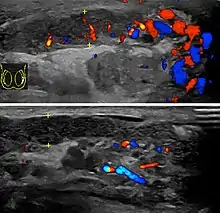

Doppler ultrasound of epididymitis, seen as a substantial increase in blood flow in the left epididymis (top image), while it is normal in the right (bottom image). The thickness of the epididymis (between yellow crosses) is only slightly increased.

Epididymitis usually has a gradual onset. Typical findings are redness, warmth and swelling of the scrotum, with tenderness behind the testicle, away from the middle (this is the normal position of the epididymis relative to the testicle). The cremasteric reflex (elevation of the testicle in response to stroking the upper inner thigh) remains normal.[1] This is a useful sign to distinguish it from testicular torsion. If there is pain relieved by elevation of the testicle, this is called Prehn's sign, which is, however, non-specific and is not useful for diagnosis.[13] Before the advent of sophisticated medical imaging techniques, surgical exploration was the standard of care. Today, Doppler ultrasound is a common test: it can demonstrate areas of blood flow and can distinguish clearly between epididymitis and torsion. However, as torsion and other sources of testicular pain can often be determined by palpation alone, some studies have suggested that the only real benefit of an ultrasound is to assure the person that they do not have testicular cancer.[14]:p.237 Nuclear testicular blood flow testing is rarely used.